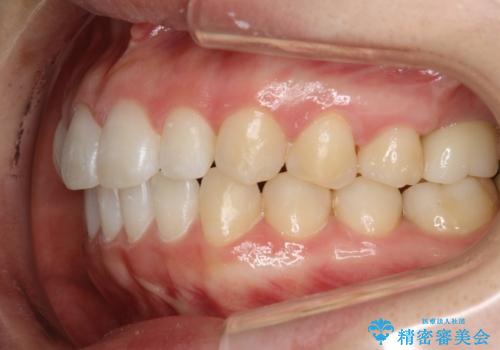

Invisalign インビザライン lite ライト 隙っ歯の改善

- 20代女性

- invisalign lite

- 6ヶ月

- マウスピース矯正による隙間の閉鎖を計画しました。

簡便な処置のため、ライトを選択しました。

かみ合わせが深くない空隙歯列は、最も簡単にその改善が見込まれます。